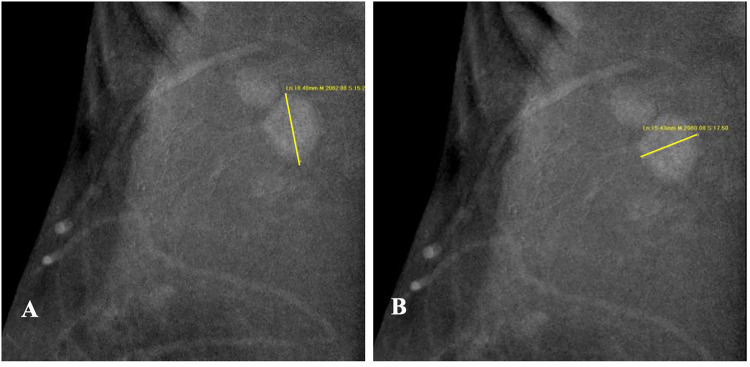

本研究旨在评估一个可解释的机器学习模型在预测术前腋窝淋巴结转移方面的性能,该模型使用原发乳腺癌和来自对比增强乳房x线摄影(CEM)和超声(US)乳房成像报告和数据系统(BI-RADS)的淋巴结特征。方法回顾性研究纳入诊断为原发性乳腺癌的患者。两名经验丰富的放射科医生根据CEM和US图像从病变的最大横截面和腋窝淋巴结中提取BI-RADS特征,创建三个数据集。每个数据集将训练六个基本模型来预测腋窝淋巴结,病理结果作为金标准。前3个模型用于训练5个集成模型。此外,采用SHapley加性解释(SHAP)来解释最优模型。采用受试者工作特征曲线(ROC)和AUC评价模型的性能。结果本研究共纳入292例女性患者,其中99例有腋窝淋巴结转移,193例无腋窝淋巴结转移。超声BI-RADS联合CEM预测腋窝淋巴结转移的效果最好。其中,LightGBM的AUC(0.762)和特异性最高(86.67%),而以RF为元模型的集合模型的AUC(0.754)和特异性最高(83.33%)。SHAP确定的最重要的变量是CEM重组图像中淋巴结的长直径,以及低能图像中淋巴结的完整形态。结论基于CEM和US BI-RADS特征的机器学习模型可以准确预测乳腺癌患者术前腋窝淋巴结转移,为乳腺癌患者的临床决策提供有价值的工具。

IntroductionThe study aims to evaluate the performance of an interpretable machine learning model in predicting preoperative axillary lymph node metastasis using primary breast cancer and lymph node features derived from contrast-enhanced mammography (CEM) and ultrasound (US) breast imaging reporting and data systems (BI-RADS).MethodsThis retrospective study included patients diagnosed with primary breast cancer. Two experienced radiologists extracted the BI-RADS features from the largest cross-section of the lesions and axillary lymph nodes based on CEM and US images, creating three datasets. Each dataset will train six base models to predict axillary lymph nodes, with pathological results serving as the gold standard. The top three models were used to train the five ensemble models. Additionally, SHapley Additive exPlanations (SHAP) was used to interpret the optimal model. The receiver-operating characteristic curve (ROC) and AUC were used to evaluate model performance.ResultsThis study involved 292 female patients, of whom 99 had axillary lymph node metastasis and 193 did not. The combination of CEM and ultrasound BI-RADS demonstrated the best performance in predicting axillary lymph node metastasis. Among these, the LightGBM achieved the highest AUC (0.762) and specificity (86.67%, while the ensemble model using RF as the meta-model had an AUC (0.754) and specificity (83.33%. The most important variables identified by SHAP were the long diameters of the lymph nodes in the CEM recombined image, along with their complete morphology in the low-energy image.ConclusionThe machine learning model using CEM and US BI-RADS features accurately predicted axillary lymph node metastasis before surgery, thereby serving as a valuable tool for clinical decision-making in patients with breast cancer.